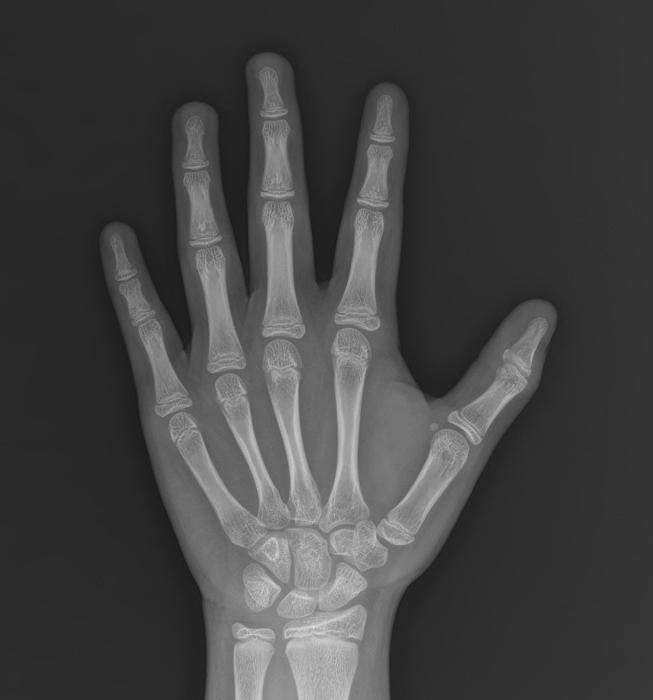

현재 치료 9개월 차, 일단 치료 한 달 만에 추가적인 초경은 없었고, 뼈나이는 그동안 더 증가하지 않고 유지되었다.

키 또한 성장곡선에 따라서 성장 속도를 잘 유지하고 있는 모습이다.

치료 시작 당시 3가지 목표,

1) 초경을 멈추고 성적인 발달을 늦춘다.

2) 뼈나이를 증가하지 않도록 유지시킨다.

3) 성장속도는 또한 최대한 떨어지지 않도록 유지시킨다.

일단 9개월 동안은 이 목표를 잘 유지하고 있다. 아이가 생활습관도 잘 고치고, 치료에 잘 따라와 준 덕분이다.